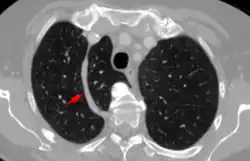

In human anatomy, an azygos lobe is a normal anatomical variation of the upper lobe of the right lung.[1] It is seen in 0.3% of the population.[2] Embryologically, it arises from an anomalous lateral course of the azygos vein,[3] in a pleural septum within the apical segment of the right upper lobe or in other words an azygos lobe is formed when the right posterior cardinal vein, one of the precursors of the azygos vein, fails to migrate over the apex of the lung and penetrates it instead, carrying along two pleural layers as the azygous fissure, that invaginates into the upper portion of the right upper lobe.[1]

An azygos lobe is usually an incidental finding on chest x-ray or CT scan. It is asymptomatic and not associated with any morbidity.[4][5] However, it can cause technical problems in thoracoscopic procedures.[6] The presence of the azygos lobe could alter the normal location of the superior vena cava or may be associated with other anomalies, including esophageal atresia or intrapulmonary right brachiocephalic veins.[7]